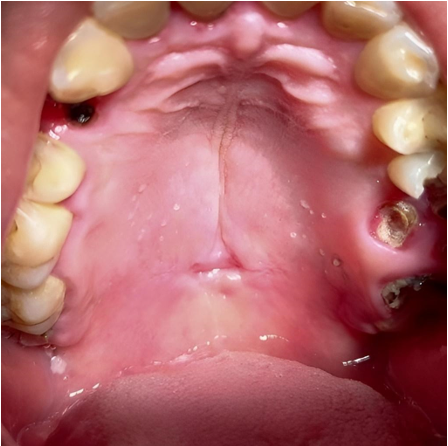

El examen físico extraoral no reveló alteraciones significativas. Intraoralmente, se observó una lesión ulcerada indolora (1,5 x 0,8 cm) con contenido necrótico y bordes ligeramente endurecidos, en la línea media del paladar blando (Figura 1), lo que generó consideraciones iniciales de sífilis y CE.

Figura 1 Apariencia clínica inicial. Lesión ulcerada indolora en la línea media del paladar blando, con contenido necrótico y bordes elevados, ligeramente endurecidos y eritroplásicos.